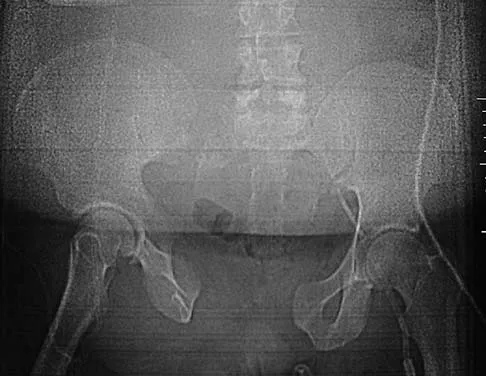

Question 571High Yield

Total hip arthroplasty in a patient with a long-standing hip fusion on the contralateral side is most likely to result in

Explanation

Contralateral total hip arthroplasty in patients with hip fusions results in a 40% higher rate of mechanical failure and loosening. During gait, motion of the contralateral hip is increased and more time is spent bearing weight on that hip. In patients with hip fusions, gait efficiency is only 53%, with a greater rate of oxygen consumption. Garvin KL, Pellicci PM, Windsor RE, et al: Contralateral total hip arthroplasty or ipsilateral total hip arthroplasty in patients who have long-standing fusion of the hip. J Bone Joint Surg Am 1989;71:1355-1362. Gore DR, Murray MP, et al: Walking patterns of men with unilateral surgical hip fusion. J Bone Joint Surg Am 1975;57:759-765.